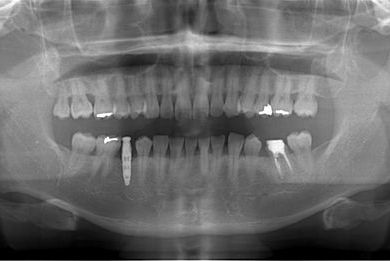

| 性別/年齢 | 男性 / 37歳 | ||||||||||||||||||||||||||||||||

| 主訴 | 前歯(2本)の欠けの治療 | ||||||||||||||||||||||||||||||||

| 治療方針 | 右下欠損部分をインプラント治療にて、機能的・審美的回復を行う。 | ||||||||||||||||||||||||||||||||

| 治療内容 | インプラント1本、メタルボンドセラミッククラウン1本 | ||||||||||||||||||||||||||||||||